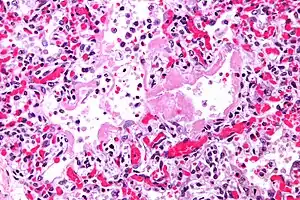

| Micrograph of diffuse alveolar damage, the histologic correlate of acute interstitial pneumonitis. H&E stain. | |

Rapid progression from initial symptoms to respiratory failure is a key feature. An X-ray that shows ARDS is necessary for diagnosis (fluid in the small air sacs (alveoli) in both lungs). In addition, a biopsy of the lung that shows organizing diffuse alveolar damage is required for diagnosis. This type of alveolar damage can be attributed to nonconcentrated and nonlocalized alveoli damage, marked alveolar septal edema with inflammatory cell infiltration, fibroblast proliferation, occasional hyaline membranes, and thickening of the alveolar walls. The septa are lined with atypical, hyperplastic type II pneumocytes, thus leading to the collapse of airspaces. Other diagnostic tests are useful in excluding other similar conditions, but history, X-ray, and biopsy are essential. These other tests may include basic blood work, blood cultures, and bronchoalveolar lavage.